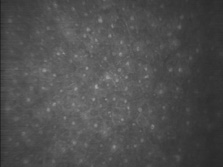

When viewed with electron microscopy, Bowman's layer appears as a felt-like composite of randomly oriented, striated collagen fibrils dispersed throughout an amorphous matrix (Fig. 12). In an adult, this layer is approximately 8 to 12 μm thick, being slightly thicker in the corneal periphery.21 Bowman's layer is acellular, except for nerve axons coursing toward the epithelium.46 Historically, electron microscopy has suggested a lack of keratocyte (fibroblast) cells within Bowman's layer, which called into question its ability to regenerate after injury or that keratocytes could migrate into Bowman's layer. In confocal microscopy views of the living eye, numerous keratocytes are observed at the level of Bowman's layer (Fig. 13).

Fig. 13. Confocal microscopic transverse image of the human Bowman's layer in vivo. Nerve axons course freely through the structure and keratocyte nuclei appear numerous and more refractile than deeper in the stroma. (500×). (Courtesy of Nidek Technologies.)